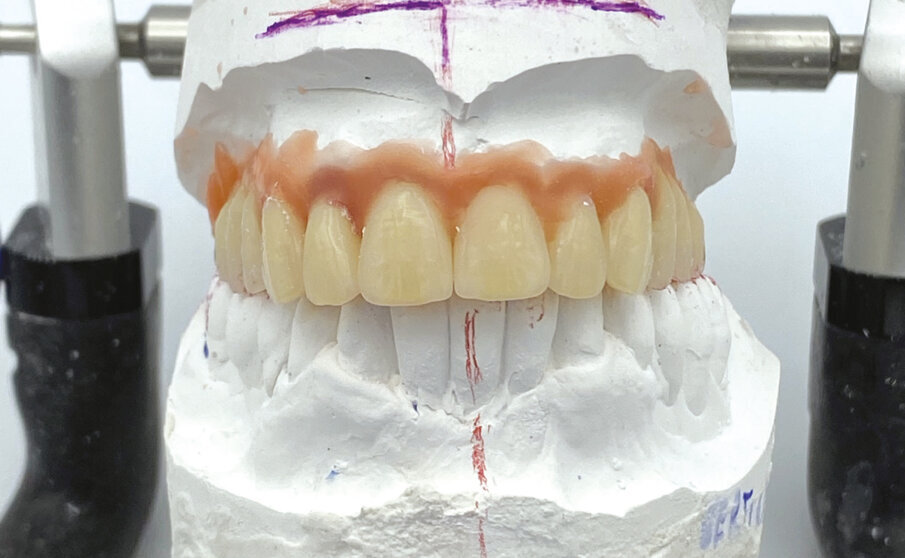

Nel laboratorio odontotecnico vengono messi in articolatore i modelli iniziali e si esegue uno studio del caso con Digital Smile Design e della situazione occlusale, per valutare eventuali rialzi della dimensione verticale e le correzioni estetiche. Le informazioni così ottenute vengono riportate nella ceratura diagnostica che in questo caso è un montaggio diagnostico/definitivo (Fig. 3). Definitivo in quanto si utilizzano già i denti del lavoro finale per il montaggio diagnostico, che vengono sfruttati per realizzare due protesi identiche in resina (Fig. 4). La prima verrà consegnata alla paziente immediatamente dopo aver inserito gli impianti. La seconda diventerà una dima protesica per la realizzazione della protesi definitiva, che verrà applicata a 7 giorni dall’intervento chirurgico.

Fig. 3 - Montaggio diagnostico.

Fig. 4 - Due protesi in resina bianca: una diventerà il provvisorio immediato per il paziente, l’altra la dima protesica.